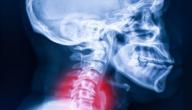

• الرقبة: يُعرف بخلل التوتر العنقي، وفيه تؤدي التقلصات إلى التواء الرأس واستناده على جانب واحد، أو ميلانه إلى الأمام أو الخلف، مما قد يسبب الألم في بعض الأحيان.